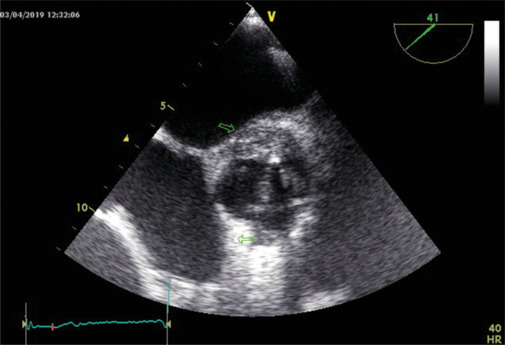

Abstract Image